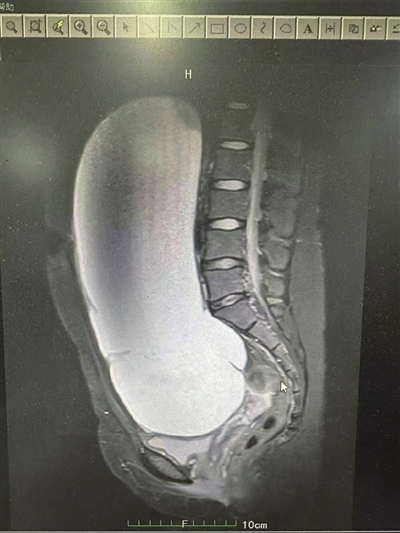

还在读大学的通山女孩小玲(化名),三个月前,肚子莫名其妙越长越大,到医院一查,竟是腹部长出了一个巨大的肿瘤,这让小玲及其全家人寝食难安,近日,小玲在武大中南医院咸宁医院接受了腹腔镜下卵巢囊肿剥除术,经医生“抽丝剥茧”的治疗,一个大约30×23厘米大小的肿瘤被成功摘除。

然而,随着时间的流逝,小玲发现自己的腹部快速膨胀,而食欲却日渐减退,稍微进食便感到腹胀难耐,她当即将这一情况告诉了家人和亲友,引起全家人及亲友的高度重视。在亲戚的介绍下,小玲的姐姐带她来到武汉大学中南医院咸宁医院妇科进行进一步诊治,经过B超检查,医生发现小玲的腹内包块已接近30厘米大小,几乎占据了她的整个盆腹腔,这一检查结果,当即就吓坏了小玲姊妹俩,同时也引起了妇科主任余晓茹的高度关注。

小玲入院两天后,余晓茹主任及佘静医生为小玲实施了腹腔镜探查术,术中看到小玲腹内的肿瘤达到30×23厘米大小,来源于左侧卵巢。为确保手术顺利进行,医生们巧妙地扩大了脐部切口,并在严格措施保护下,成功引流出了约4500毫升的囊液。随后,小心翼翼地将左侧卵巢提出腹腔,完整地剥除了肿瘤组织,并巧妙地将剩余的卵巢组织缝合成型,以期最大限度地保留卵巢正常功能 。术中,将切下来的卵巢肿瘤组织送快速病检,幸运的是,病检结果并未发现恶性病变的迹象。术后,小玲的恢复情况非常良好,后续的病检结果也再次证实了肿瘤的非恶性。